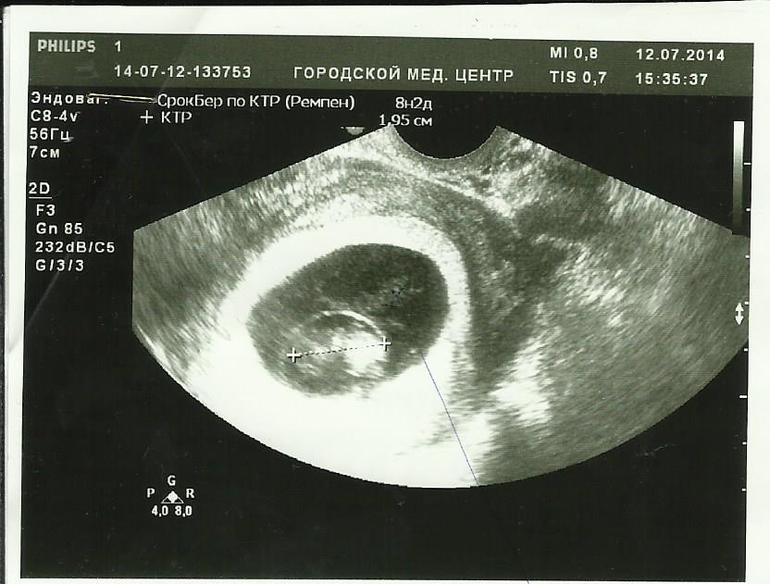

На этом снимке , то что похоже на измерение эмбриона, врач мне объяснила, что ..... эмбрион находится в дополнительном пузыре который говорит о патологии а там куда ведет полоса от шариковой ручки , это (как она написала) эхо визуализируется , на словах она сказала, что жидкость в нутри дополнительного пузыря плотная, не однородная и это говорит о внутриутробной инфекции. Светлое широкое кольцо обрамляющее пузырь говорит о том, что в матке идет воспалительный процесс.

На этом снимке врач отметил " чрезмерно толстую пуповину "С казала , что ребенку очень тяжело дышать, ему не хватает кислорода! И опять сделала акцент на том , что пузыря второго не должно быть вообще! То , что он есть ,это очень плохо! Мне лучше прервать беременность т.к ребенок может родится с разными отклонениями сердечной и дыхательной системами! А пить антибиотики на этом сроке опасно тем , что ребенок так же может родиться с отклонениями......